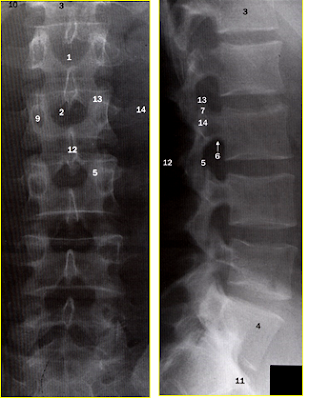

Chụp x-quang

- Cho biết đường cong SL

- Kích thước và vị trí đốt sống.

- Khoang gian đốt và đĩa đệm.

- Kích thước lỗ tiếp hợp.

- Các dị tật

Chụp CLVT (CT

Scanner)

Chẩn đoán CX đối với nhiều thể TVĐĐ

Chẩn đoán PB với hẹp ống sống, u tuỷ

Chụp CHT (MRI)

Chẩn đoán XĐ TVĐĐ, nó cho biết vị trí và mức độ thoát vị,

cho biết về xương và các phần mềm xung quanh.